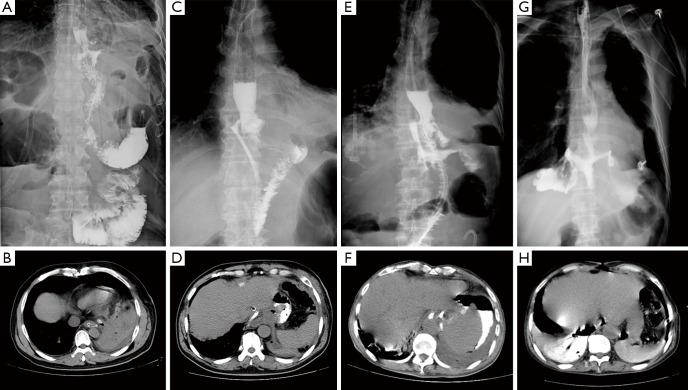

The clinical data of 57 patients with superior anastomotic leakage after surgery for AEG in the Affiliated Cancer Hospital of Zhengzhou University from January 2017 to March 2019 were retrospectively analyzed, including 27 cases referred from external hospitals and 30 cases at the Affiliated Cancer Hospital of Zhengzhou University. According to the diameter and risk level of anastomotic leakage, the high anastomotic leakage is divided into types I, II, III, and IV.

Patients with preoperative comorbidities or those treated with the transabdominal approach or laparoscopic surgery often had type I and type II anastomotic leakage; meanwhile, patients with preoperative comorbidities and sacral perforation or those treated with a thoracic and abdominal approach or open surgery often had type III and IV fistula. The difference between types I-II and types III-IV was statistically significant (P<0.05). The mortality rate of patients with type III and type IV leakage was 14.8% within 90 days after operation, while no deaths occurred among patients with type I and type II leakage, and the difference in mortality between the two groups was statistically significant (P<0.05).

After surgery for AEG, suitable treatment measures should be adopted according to the type of superior anastomotic leakage that occurs. Types III and IV superior anastomotic leakages are associated with higher mortality and require greater attention from surgeons.